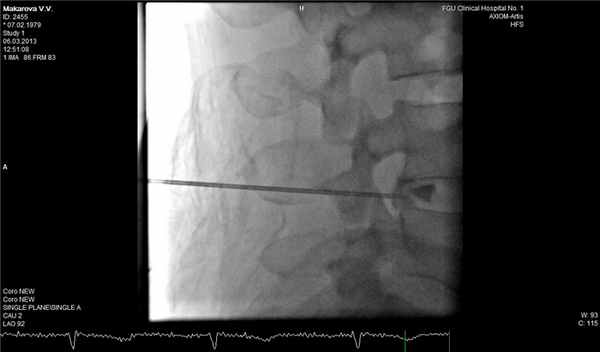

В трудных для диагностики случаях можно дополнительно к МРТ позвоночника применить дискографию, которая достоверно подтвердит или опровергнет диагноз рецидивной грыжи диска. Эпидурография также может быть полезна для оценки состояния корешка в позвоночном канале.

![]()

Фораминальная рецидивная грыжа 5 мм. Дискография.

Сдавление корешка L4 в корешковом канале, несмотря на малые размеры грыжи. Эпидурография.